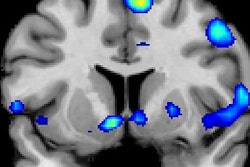

The group looked at fMRI scans of 22 girls to analyze the relationship between engagement and verbal interactivity while a mother reads to her child. The children who showed greater interest in the reading interaction showed increased activation in right-sided cerebellar areas of the brain, which are associated with cognitive skills connected to language and executive function.

Evidence shows the benefits of shared reading may improve literacy and brain development. Image courtesy of Cincinnati Children's.

Evidence shows the benefits of shared reading may improve literacy and brain development. Image courtesy of Cincinnati Children's."The takeaway for parents in this study is that they should engage more when reading with their child, ask questions, have them turn the page, and interact with each other," said lead author Dr. John Hutton, a pediatrician at Cincinnati Children's Hospital, in a statement.